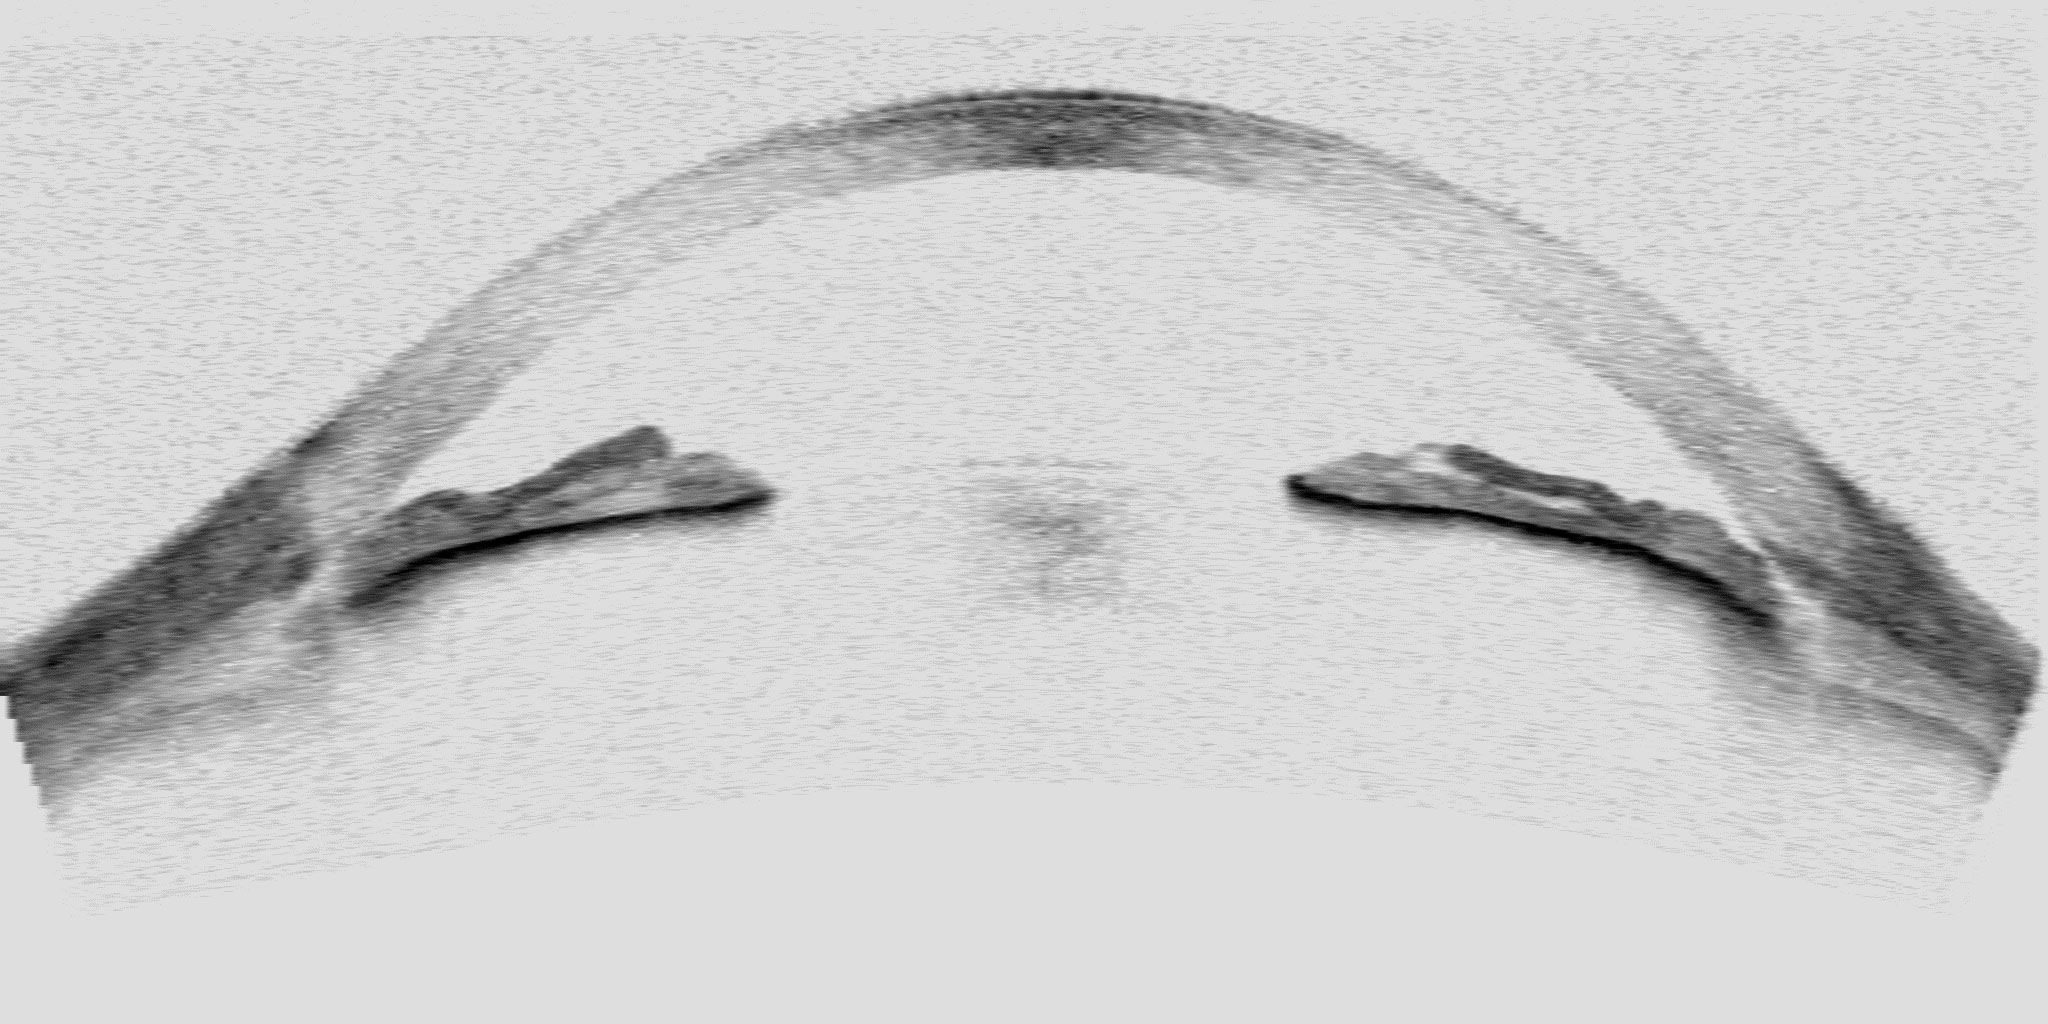

This is the first tomography map for diagnosing glaucoma, which consists of 1,000 tomographic images of the iridocorneal angle acquired using optical coherence tomography (OCT) and arranged on a grid, so that patients can easily understand the condition of their eyes by identifying them somewhere between the closed-angle area (severe) and the open-angle area (mild).

According to Pablo Amil, “when it comes to diagnosing, ophthalmologists just have a single tomographic image of their patient’s eye that shows the state of the iridocorneal angle. If the angle is closed, the drainage of the intraocular fluid is blocked and intraocular pressure rises. Doctors usually give quite accurate diagnosis, but patients lack comparative tools that help them decide whether they wish to undergo surgery or not. My work will allow patients to easily and objectively compare, through an image map, the severity of their condition and help them decide on or against surgery”.

Pablo Amil has created the first tomography map for diagnosing glaucoma with an artificial intelligence algorithm, to which he applied 1,000 images of iridocorneal angles. He then sorted and arranged them on a grid according to severity (severe, moderate and mild) and compared this distribution with 160 diagnoses made by ophthalmologists. The correlation result is almost the same between the map created by Amil and the severity diagnosed by ophthalmologists.